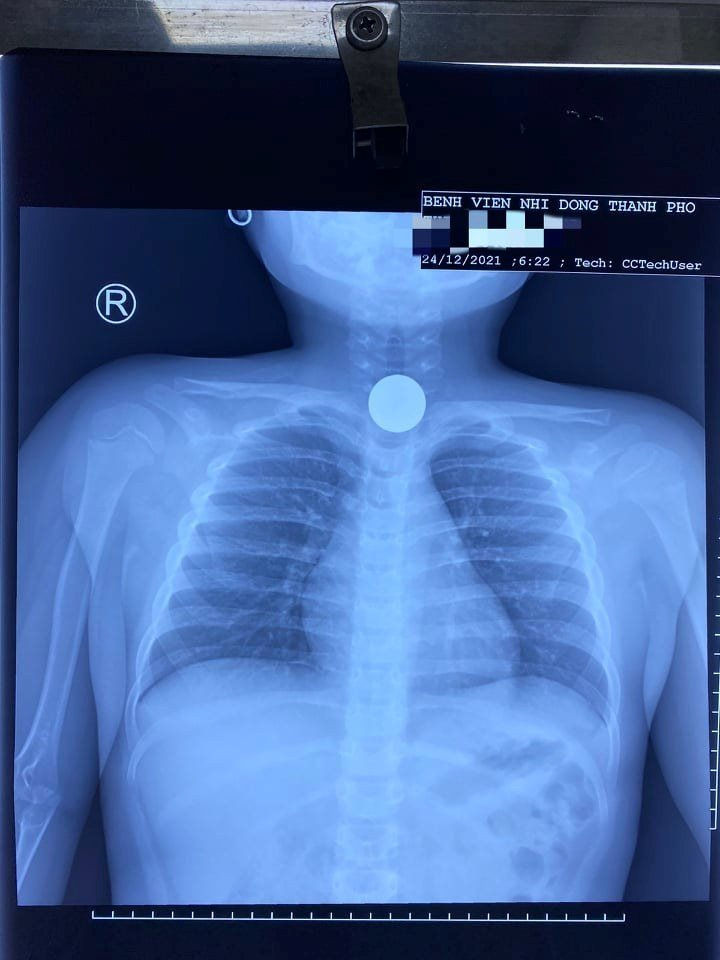

Kết quả trên hình phim, các bác sĩ phát hiện một vật cản âm tròn đều như mô tả đồng xu, mật độ như kim loại.

Gia đình đã tức tốc đưa trẻ vào viện. Kết quả trên hình phim, các bác sĩ phát hiện một vật cản âm tròn đều như mô tả đồng xu, mật độ như kim loại.